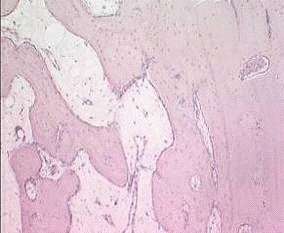

. Исследования тонкой структуры костного матрикса пластинчатых и

трубчатых костей в норме методом сканирующей электронной микроскопии (10

образцов).

2. Исследования тонкой структуры костного матрикса пластинчатых и